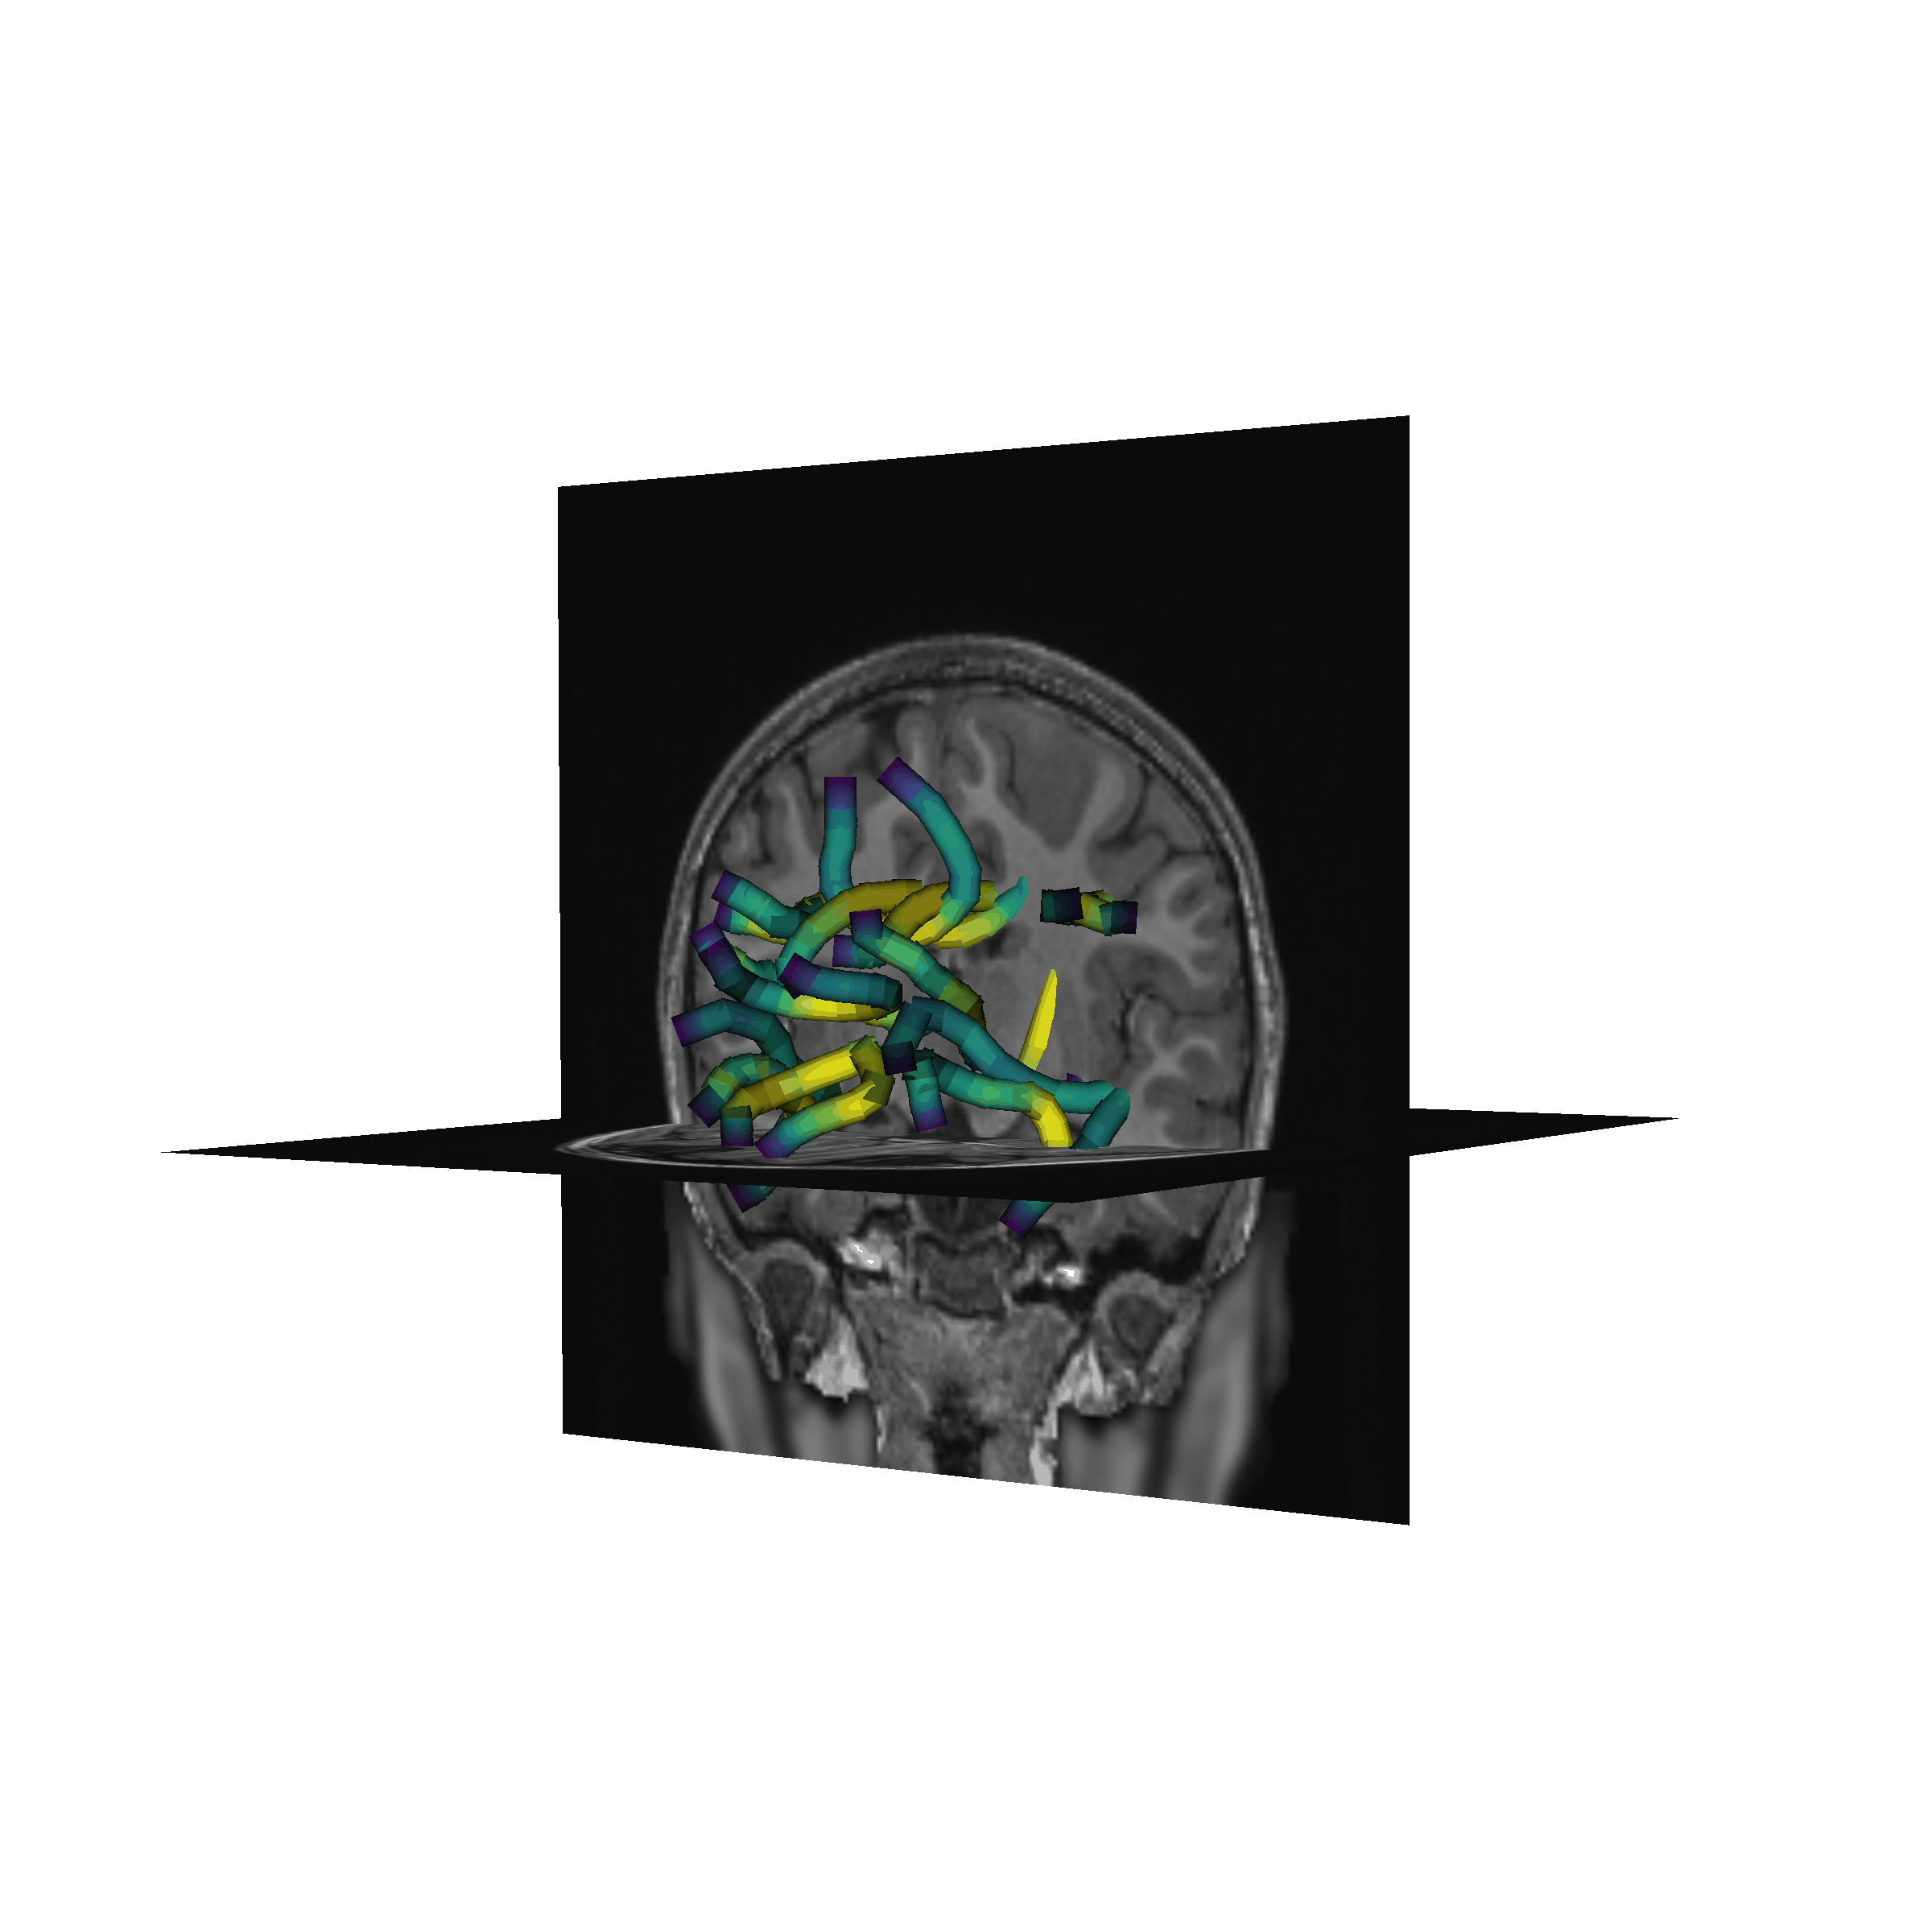

Basser (1994), Basser and Pierpaoli (1996)